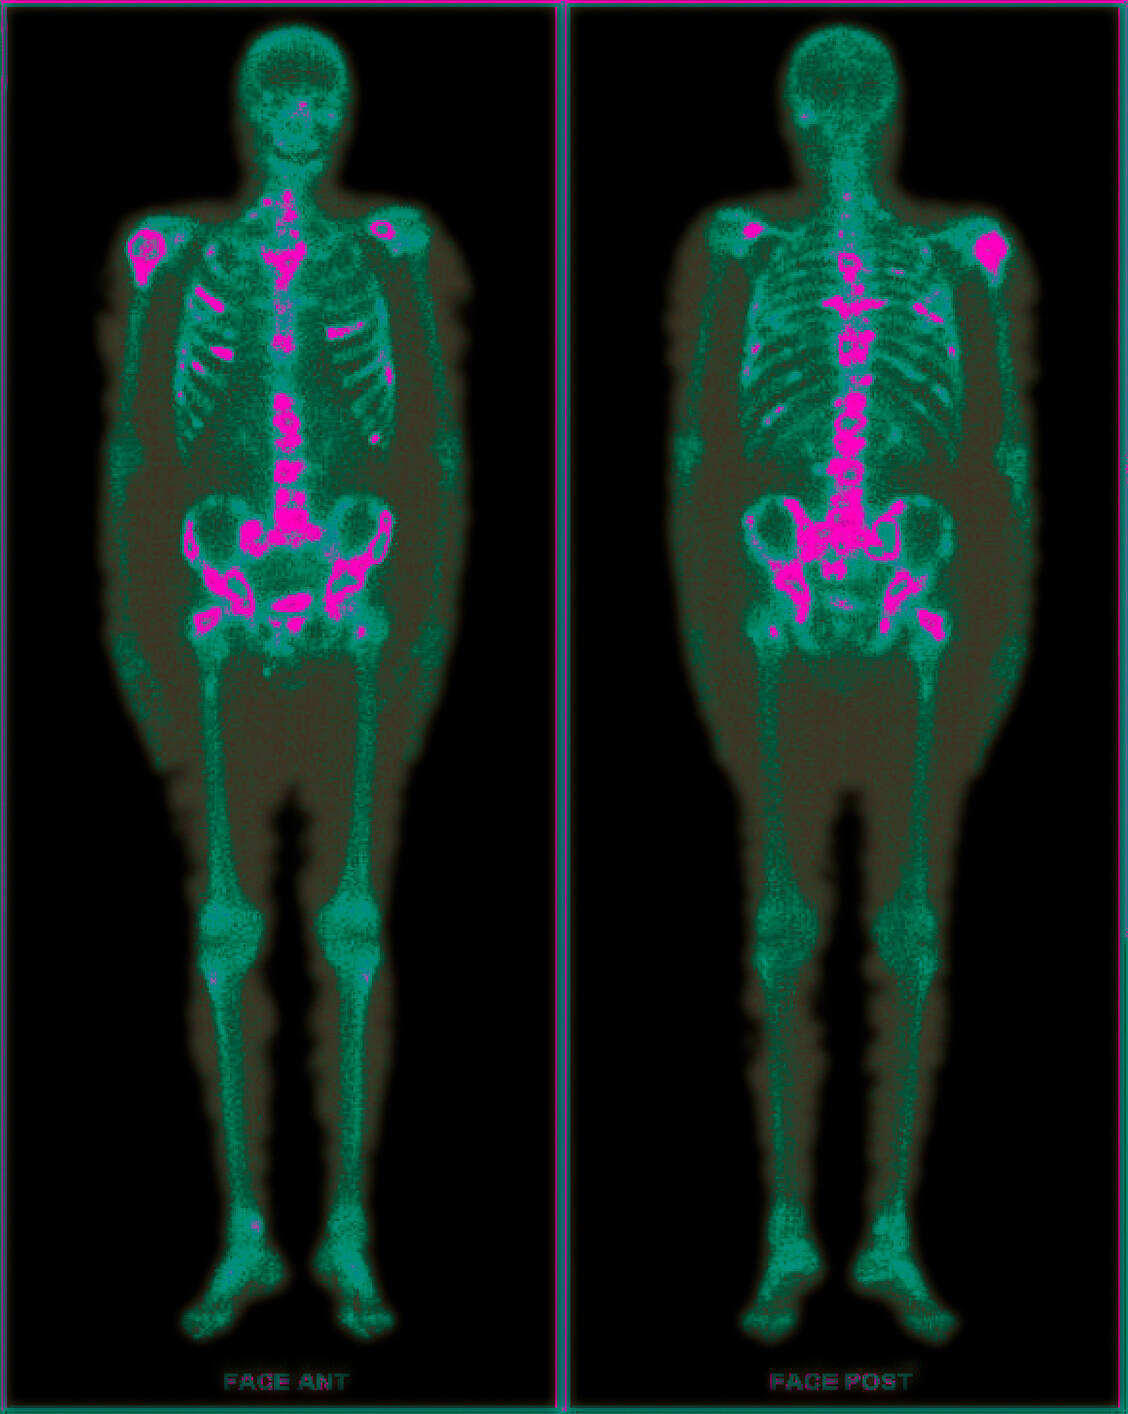

Der PET-Scan zeigt Metastasen bei einem Mann mit Prostatakrebs. / Foto: Your Photo Today

Bei vielen Tumoren treten Knochenmetastasen auf, beispielsweise beim fortgeschrittenen Prostatakarzinom. Ihnen kommt man mit [18F]Fluorid auf die Spur, einem der ältesten nuklearmedizinischen Tracer, der sehr schnell im Knochen akkumuliert.

Die Fluorid-Ionen wandern schnell per Diffusion in den Extrazellularraum der Knochen, wo sie in einer Austauschreaktion mit einer Hydroxyl-Gruppe des Hydroxylapatits (früher meist Calciumapatit genannt) als Fluorapatit in die Knochenmineralien eingebaut werden. Diese Reaktion korreliert mit der Knochenneubildung und kann mit PET-Bildgebung dargestellt werden.

Neben dem Nachweis von Knochenmetastasen bei Prostatakrebs wird das Verfahren häufig bei neuroendokrinen Tumoren angewandt, die nur langsam wachsen. Die dort auftretenden Knochenmetastasen bestehen nur aus osteoblastischen Zellen wie das umgebende Knochengewebe. Bei einer Röntgenaufnahme fallen sie daher nicht auf. Sie sind nur mit einem Radiotracer detektierbar.